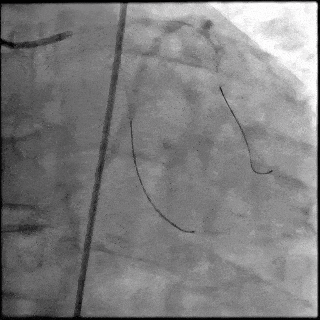

5月28日8:00,葛均波院士团队在中山医院16号楼16楼中伟厅成功连线喀什二院导管室,沪喀远程手术正式开始。8:35,新疆喀什二院导管室内股动脉入路通路建立后,行左右冠脉造影示左前降支中段存在85%的严重狭窄,狭窄位于血管分叉路口且紧邻心肌桥;且左回旋支中段近乎闭塞,血管细窄且迂曲,病变弥漫。8:59,葛院士于上海操控血管介入机器人主端,将指引导管送至左冠脉开口,并操控主支导丝和分支血管保护导丝通过狭窄病变,后送至前降支和对角支血管远端以建立轨道,同时利用介入机器人的微速调整功能避开心肌桥,以亚毫米级精准定位释放1枚支架。在成功处理患者左前降支病变后,葛院士通过搓捻机械操纵杆,远程精细调整导丝“进攻”方向,顺利通过左回旋支次全闭塞病变。因血管相对细小且病变弥漫,葛院士决定采用单纯球囊扩张术处理,即刻造影提示几乎无残余狭窄,避免了额外的支架植入。10:10,撤出所有导丝及导管,手术顺利结束。

【DSA图2.前降支支架释放】